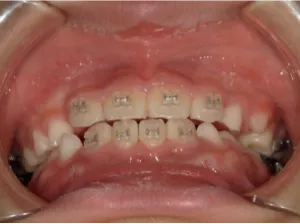

治療中④小2(8y2m)~小3(9y1m):QHとBHで拡大・アーチ形態の修正、ブラケットで前歯の並べ替えまで終了

| 行ったご提案・診断内容 | 成長期に行う治療と咬合治療をご提案 受け口用ファンクショナルアプライアンス(写真②③)からスタートし、小2以降で上下顎の拡大・歯列弓の形態修正・前歯の並べ直し(写真④)を行いその後、モノブロック(筋機能的咬合誘導)装置(写真⑤)へ移行し、受け口の再発予防と永久歯を適切な咬み合わせに誘導し、必要によりマルチブラケット法へ移行する治療方法を提案しました。 成長期治療(成長時期にお口の環境を整える治療) 2年生以降から 咬合治療 |

| 治療期間 | 12か月:受け口用ファンクショナルアプライアンス(写真②③) 12カ月:成長期治療の動的治療期間(写真④) 現在、成長の経過観察と咬合誘導中です(写真⑤~⑨) |